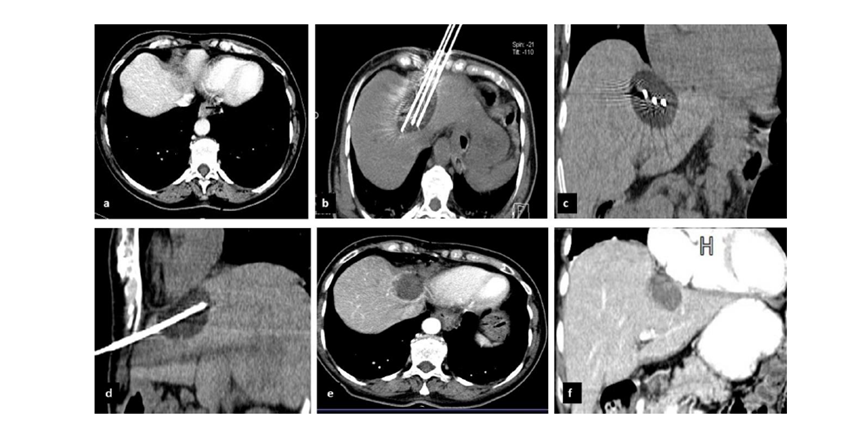

79 歲男性,肝轉移(結直腸癌)腫瘤的完全消融病例

( a ) 軸向 MRI 和 ( b ) 軸向 CT 顯示肝S8段有一個16mm的病灶,鄰近肝緣。( c )冷凍消融期間CT顯示放置了2個冷凍探針,低密度冰球包圍病灶。(d)術后1個月隨訪 CT顯示冰球?qū)膲乃绤^(qū)域,未見復發(fā)。(e)術后6個月的CT,壞死區(qū)域縮小,未見復發(fā)。(f)與基線影像(g)相比,12個月后的FDG-PET/CT顯示未見FDG攝取。

(a)軸向CT顯示病變位置毗鄰心臟和上腔靜脈(黑色箭頭)。1個月后的軸向(e)和冠狀位(f)增強CT掃描顯示低密度區(qū)域,由于肉芽組織反應引起的邊緣增強。